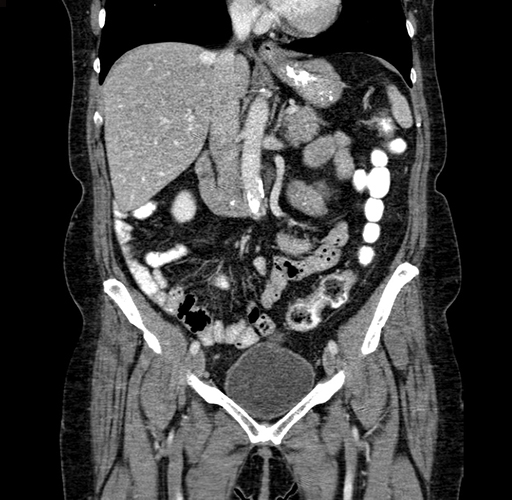

Pre-Chemo: Coronal Venous

Coronal Venous